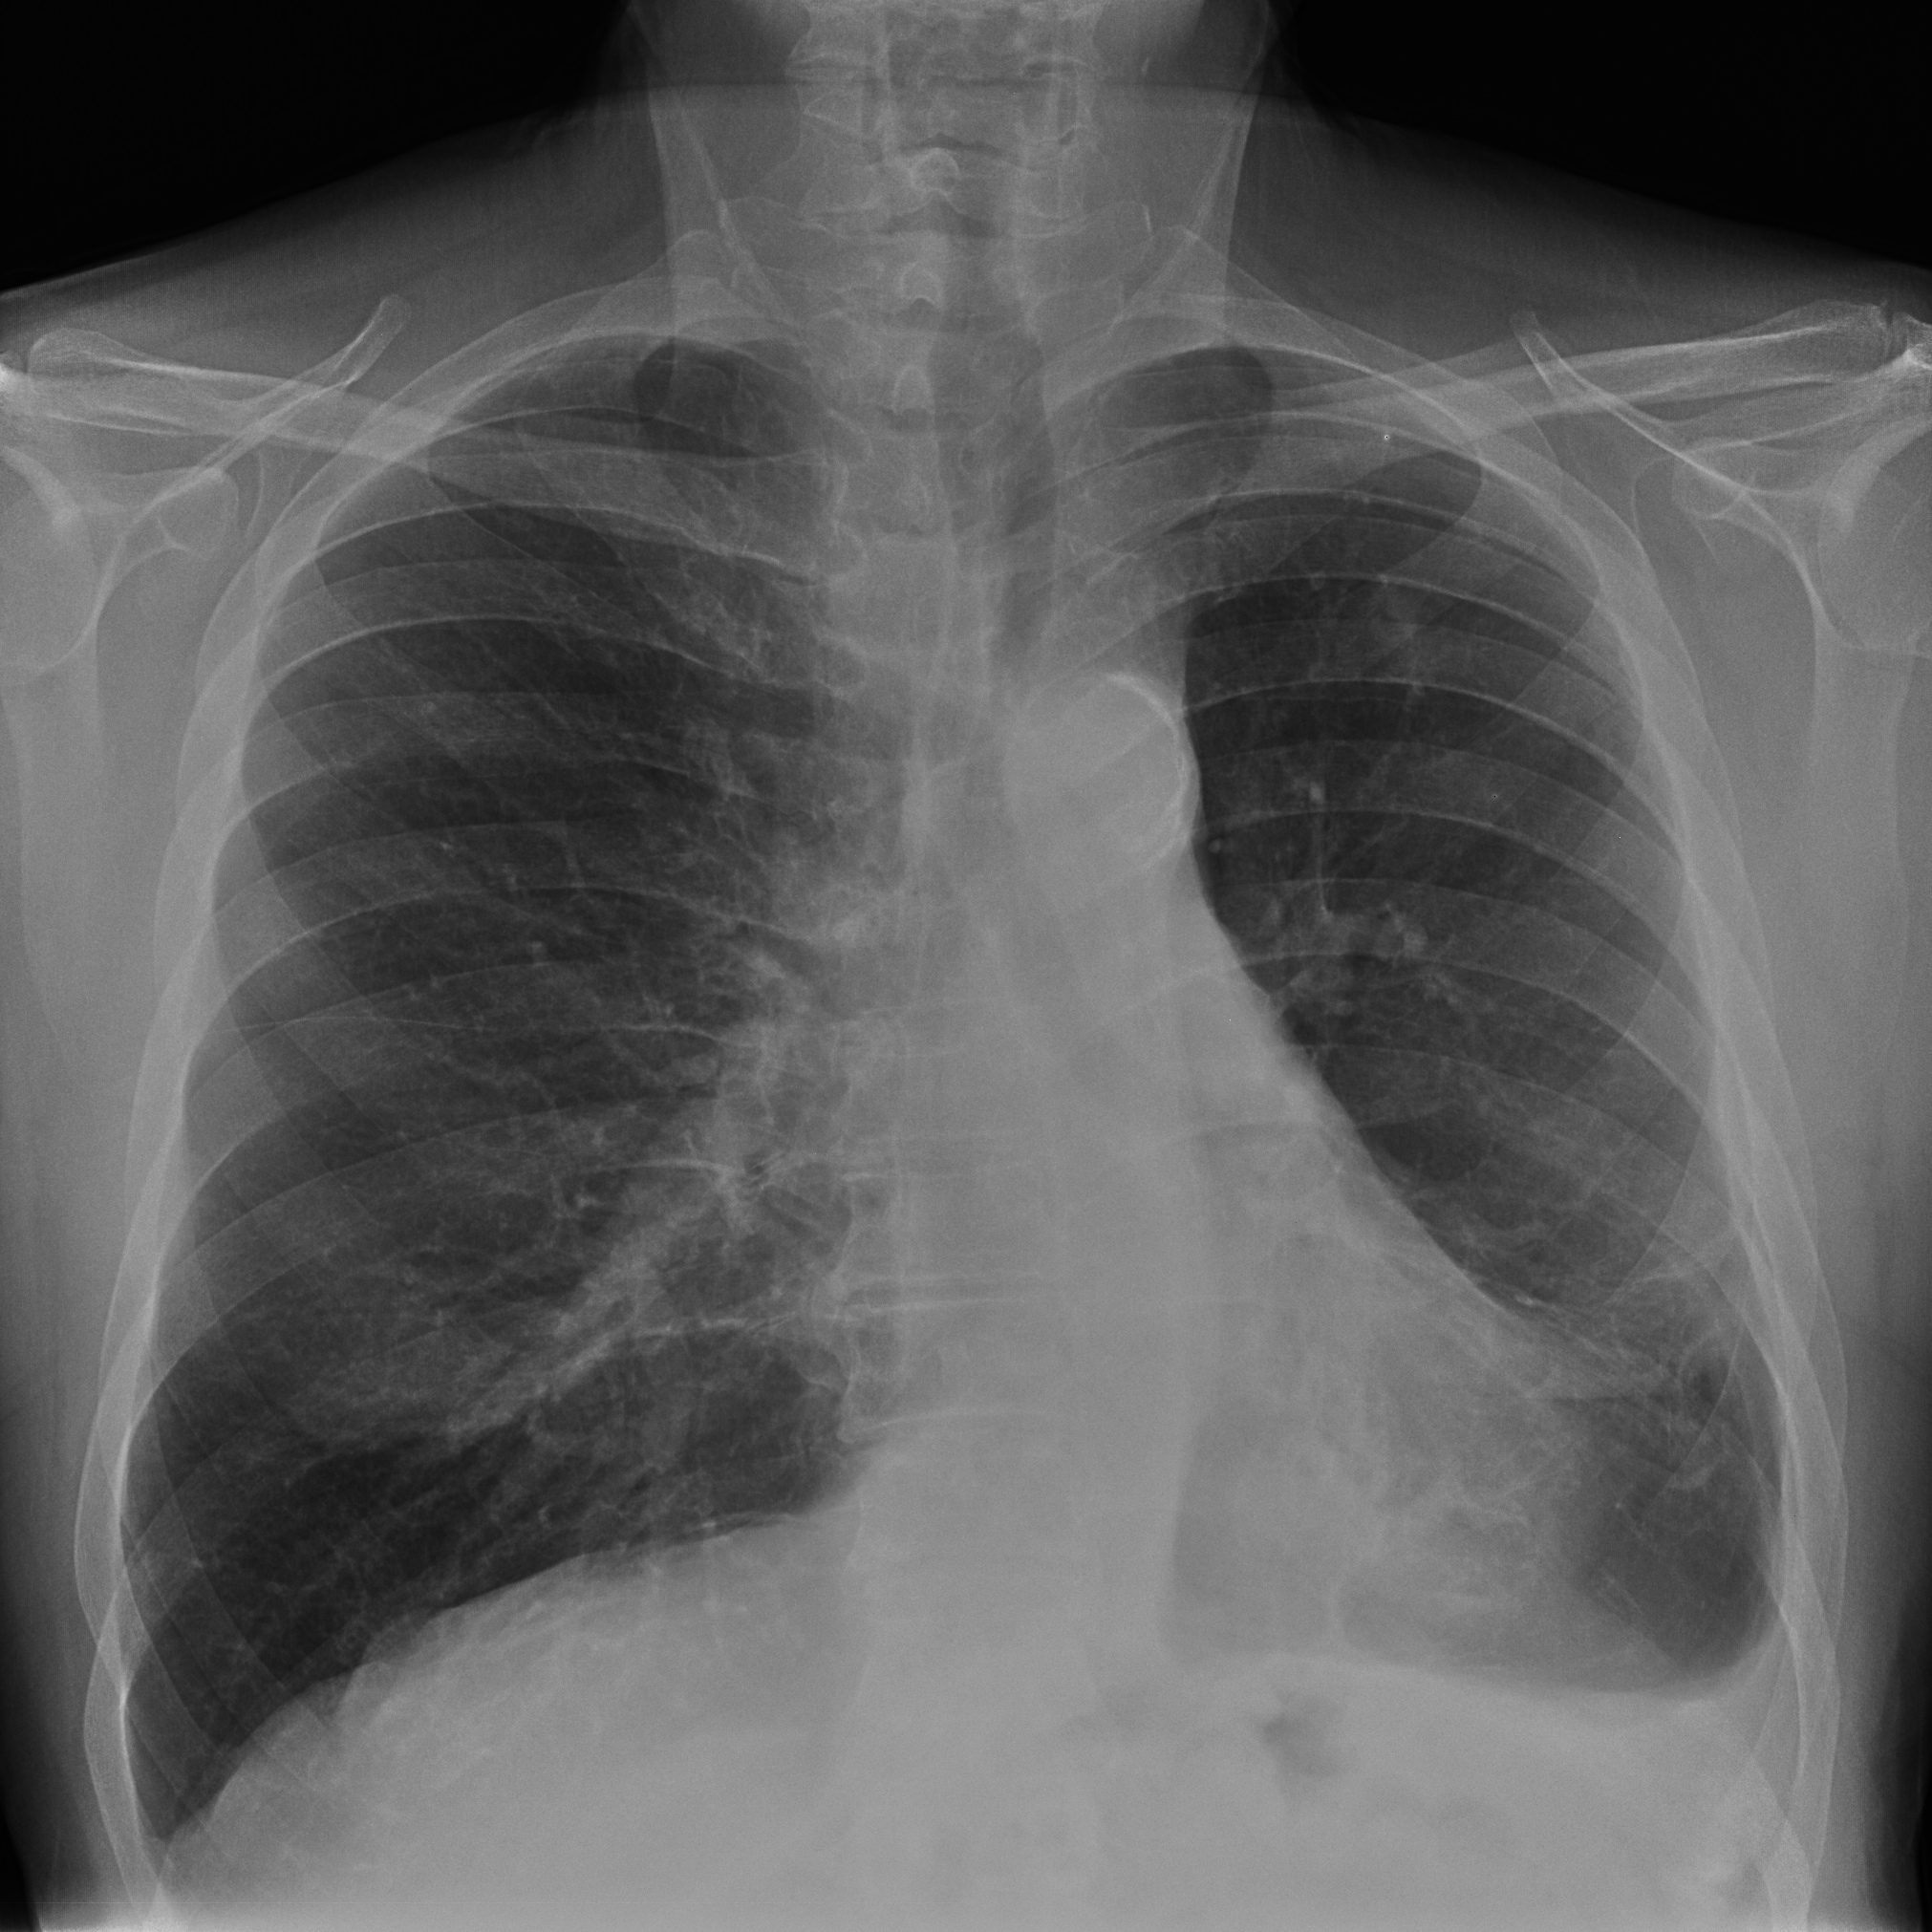

Solución: Es un estudio Normal. Silueta cardiomediastínica y parénquimas pulmonares sin alteraciones significativas.